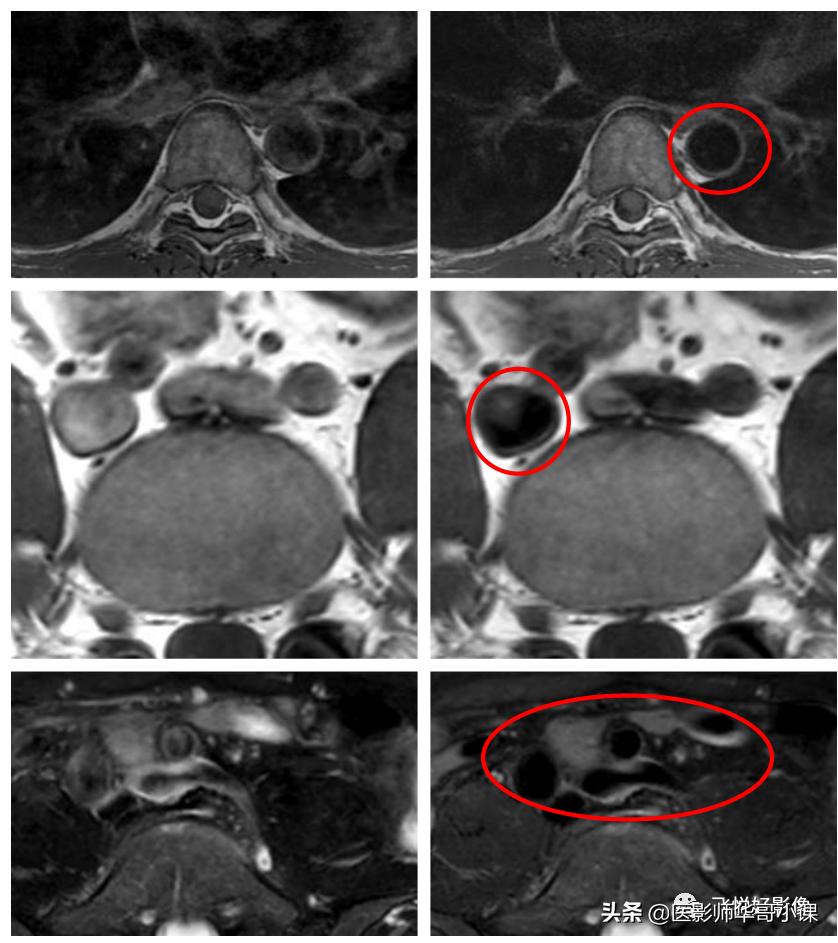

图10.左图为常规TSE图像,右图为PSS-TSE

我们可以从上图中看出,使用PSS技术,红圈中血管信号被抑制,呈低信号。